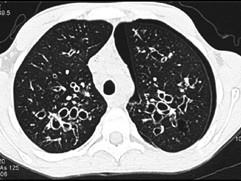

问题 男,38岁,咳嗽、咳痰、咯血,结核菌素实验(-),结合CT图像,最可能的诊断是 ( )

选项 A、间质性肺炎 B、特发性肺间质纤维化 C、肺囊虫病 D、肺囊肿 E、支气管扩张

答案 E